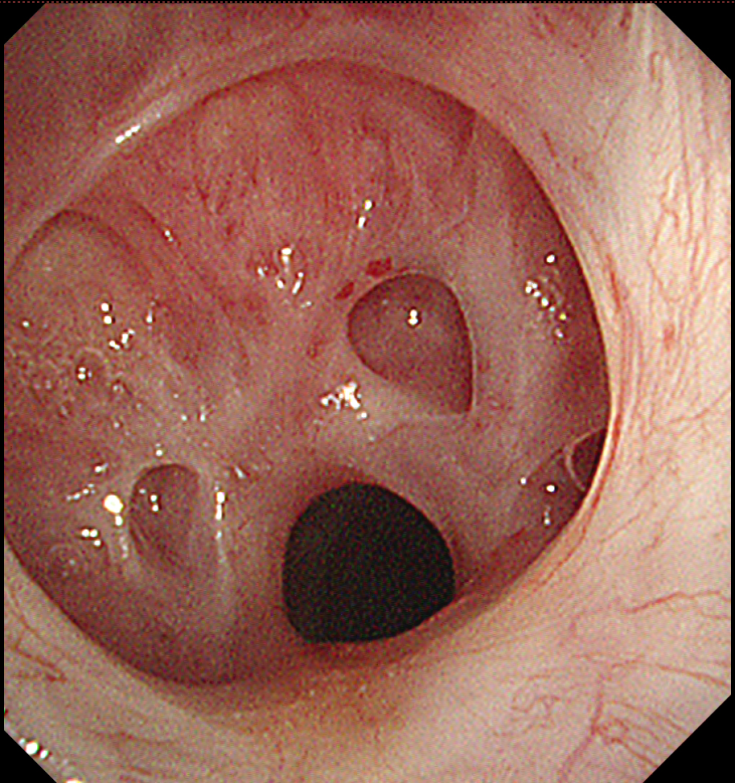

入院后经检查发现,谢先生声门下气管出现明显狭窄。导致他呼吸困难的“元凶”终于浮出水面——中央气道因肉芽组织疤痕增生,引发严重的良性中心气道狭窄。

“这相当于患者每分每秒都在通过一根饮料吸管呼吸。”CT显示,狭窄处管腔4mm,狭窄程度高达80%,狭窄段长达2厘米。广州市花都区人民医院呼吸与危重症医学科主任医师招树涛表示,一旦有少量痰液堵塞,就可能引发致命性窒息,抢救窗口期极短。

手术中,主任医师招树涛团队通过支气管镜精细操作,精准定位狭窄部位。在团队密切配合下,历时1个多小时,手术顺利完成。

当谢先生从麻醉中苏醒,立即感受到呼吸的畅快——困扰他许久的憋闷感消失。得益于微创技术创伤小、恢复快的优势,他在术后第二天便顺利出院。一周后,谢先生返院接受第二次纤支镜介入治疗巩固疗效。复查显示,其气道狭窄程度已从80%改善至20%,接近正常水平,呼吸功能基本恢复如常,如今已能自由活动,回归正常生活。